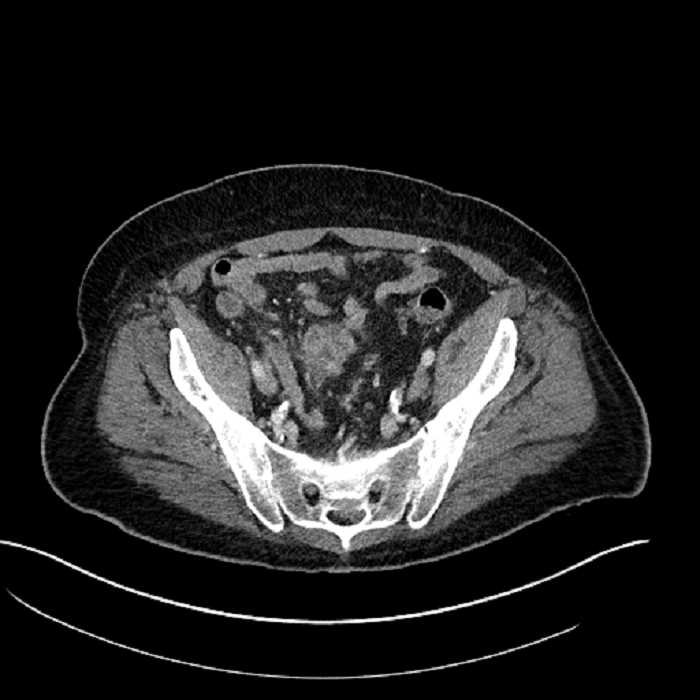

• Large fluid density structure in hepatic segments 7 and 8 measuring 10 x 7 x 7 cm with internal septation and circumferential ill-defined low density compatible with edema

• Mild mural thickening of a segment of the sigmoid colon with adjacent fat stranding and a 1.5 cm fluid and gas collection along the tip of an inflamed diverticulum

• Loss of the normal fat plane between this collection and adjacent loops of small bowel, which demonstrate mural thickening

• High grade stenosis of the left common iliac artery, with the left internal and external iliac arteries remaining patent

Acute sigmoid diverticulitis complicated by a small contained perforation and a large abscess in the right hepatic lobe. Additional small subcapsular abscesses along the anterior margin of the left hepatic lobe.

Additionally, loss of the normal fat plane between the peridiverticular collection and adjacent thickened loops of small bowel raises the potential for an enterocolonic fistula.

High grade stenosis of the left common iliac artery. The left external and internal iliac arteries are patent.

Hepatic abscess showing the double target sign with low density internally surrounded by a thin inner enhancing rim (red arrow) and ill-defined outer low density rim (yellow arrow). Blue arrow indicates an internal septation. Red arrows: additional smaller subcapsular abscesses. Red arrow: focal contained perforation associated with diverticulitis.